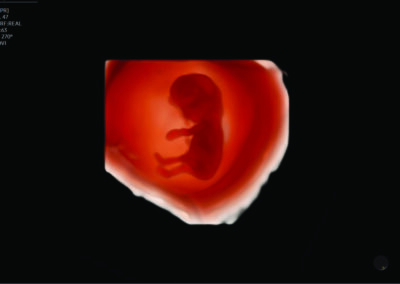

Comprehensive, advanced and expert MFM care for high-risk pregnancies